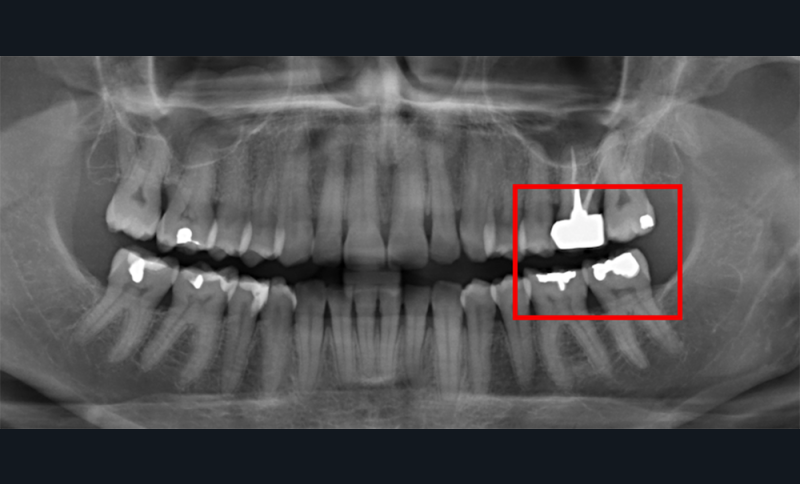

Aspect clinique et radiographique des lésions d’abrasion

Cliniquement, les lésions d’abrasion sont caractérisées par des facettes lisses, une absence de convexité et des bords à angles vifs. La flexibilité du ligament alvéolo-dentaire va entrainer un frottement au niveau des points de contact, qui peuvent se transformer en surfaces de contact (fig. 2c-d, 3 et 4b-c).

Radiographiquement, on observe une perte des cuspides et un aspect plan des faces occlusales (fig. 2a-b et 4a).